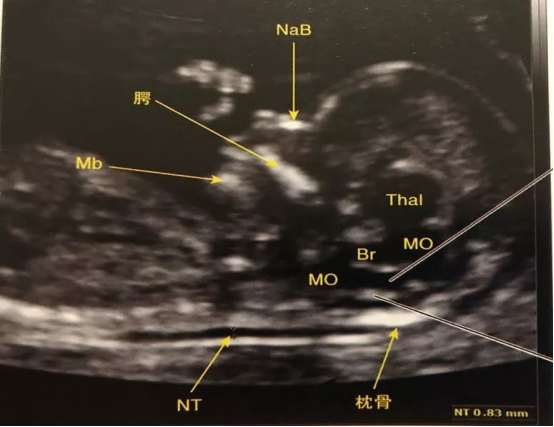

1. 颈后透明层(NT)增厚

1)是什么?孕11-13⁺⁶周时,胎儿颈后部液体积聚的厚度。正常值一般小于2.5mm或3.0mm(不同医院标准略有差异)。

2)意味着什么?NT增厚是早期筛查唐氏综合征及其他染色体异常、心脏问题的一个重要指标。厚度越高,风险相对越大。

3)怎么办?这只是一个筛查工具。如果NT增厚,医生通常会建议进行更精确的产前诊断,如无创DNA(NIPT)或羊膜腔穿刺,来明确诊断。同时,在孕中期进行详细的胎儿心脏超声检查也非常重要。